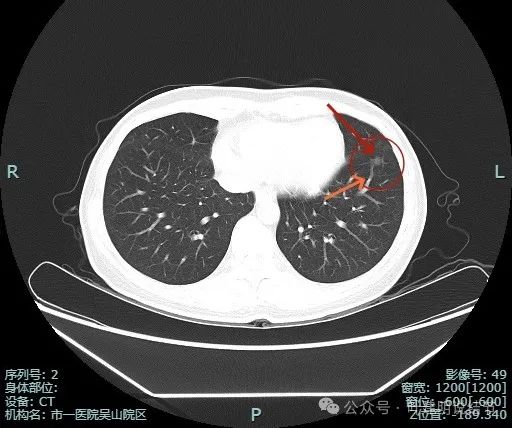

薄层影像:

病灶离叶间裂较近,几乎贴着,叶间胸膜略有牵拉向病灶侧,但力量小。可见有一细小血管走向病灶。

他处也有小血管进入,整体轮廓与边界清。

边缘显得毛糙。

边缘区也是磨玻璃密度。